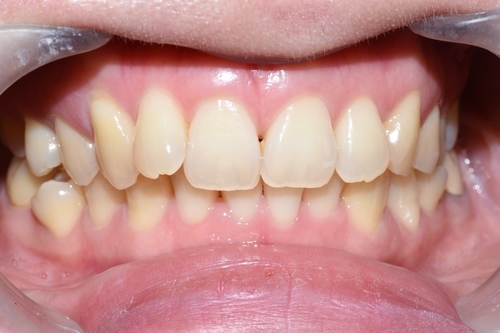

![[시청역/광화문/서대문]삐뚤삐뚤한 치아 무삭제라미네이트로 치아성형 관련 이미지 2](https://pub-9f2bb3498faf4d1d8714b41df24753e3.r2.dev/content/clinics/archive/rseeanjxfu/naver_blog/yonseiyegam/assets/by_hash/4af571c87bde6fa9f3139c67a228689e20519a09c302715b04534d61941cd6b5.jpg)

치아가 고르지 못한 상태였고

처음 상담시 교정을 추천드렸으나

환자분께서 최대한 빠른 방법을 원하셔서 교정은 원치 않으셨습니다.